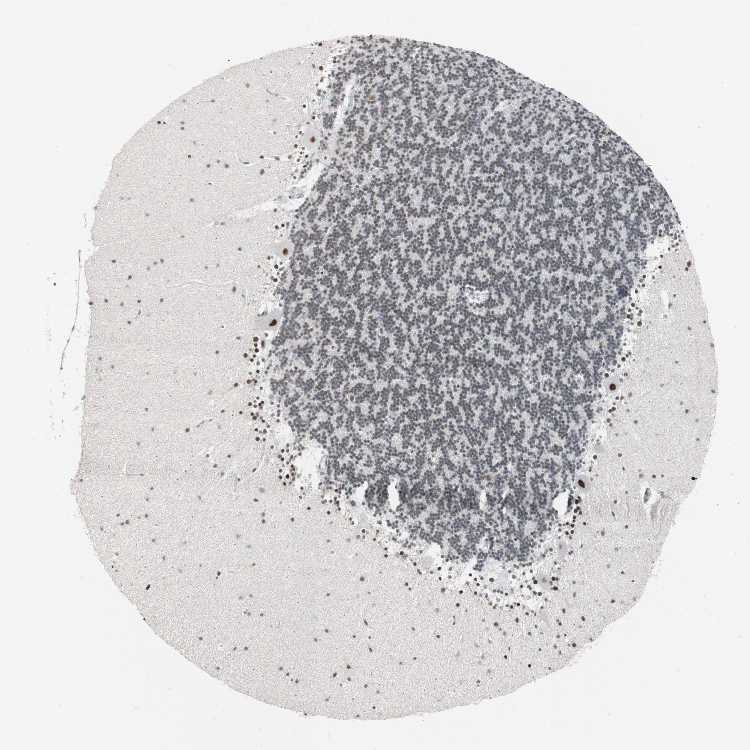

BRAIN CEREBELLUM Show tissue menu

CEREBELLUM - Expression summary

CEREBELLUM - Antibody stainingi

Antibody staining in the annotated cell types in the current human tissue is reported as not detected, low, medium, or high, based on conventional immunohistochemistry profiling in selected tissues. This score is based on the combination of the staining intensity and fraction of stained cells.

Each image is clickable and will lead to virtual microscopy that enables deeper exploration of all samples and also displays staining intensity scores, fraction scores and subcellular localization as well as patient and tissue information for each sample.

Antibody HPA005456Antibody CAB016334

Purkinje cells HighHigh

Cells in granular layer HighHigh

Cells in molecular layer HighHigh